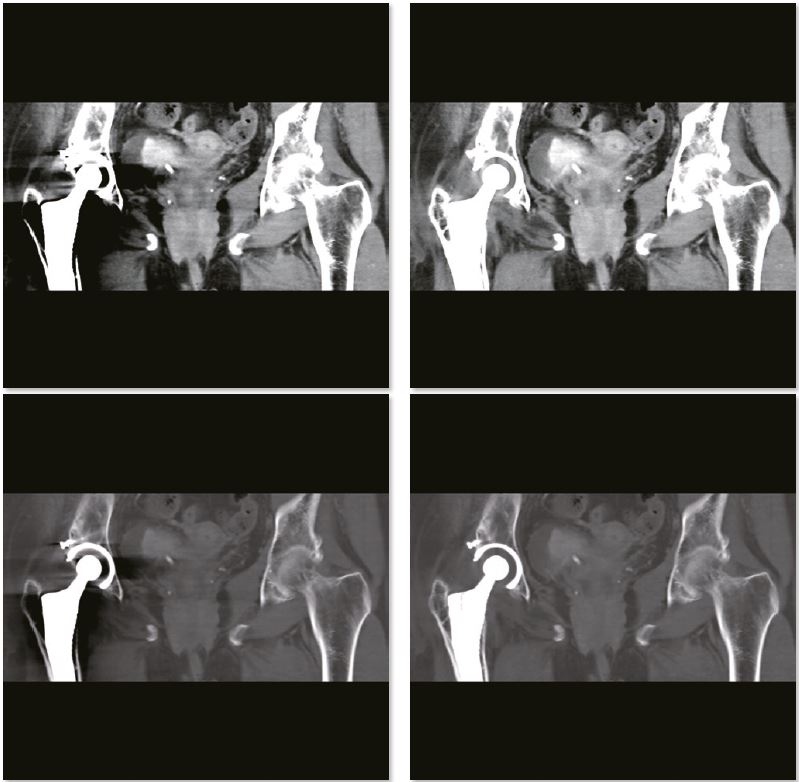

Обстеження м'яких тканин тазу

SEMAR можна вільно застосовувати, проспективно чи ретроспективно, до отриманих необроблених даних під час сканування будь-якого обсягу. У цьому випадку SEMAR застосовували для зниження металевих артефактів і отримання чіткого огляду м’яких тканин малого тазу. Пухлина сечового міхура чітко видно на реконструйованих зображеннях SEMAR.

3D зображення тазу

Звичайне зображення

Зображення з SEMAR